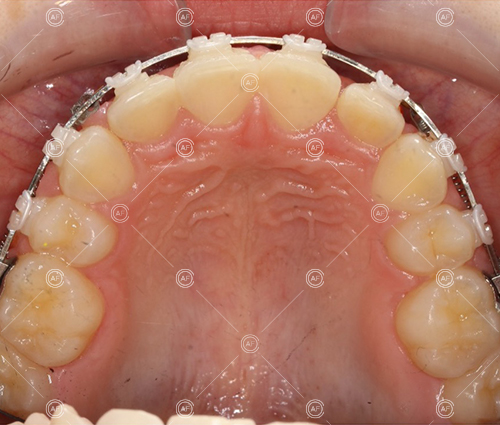

Treatment progressed by starting with thin, flexible nickel titanium archwires of a round diameter, transitioning to a rectangular nickel titanium archwire before eventually working up to a working archwire (1925 stainless steel).

Residual space from the extractions were closed using upper and lower nickel titanium closing coils. Class 2 elastics were used to facilitate space closure in order to gain class 1 buccal segments.

MH debonded in December 2020, with overall treatment time of around 14 months.